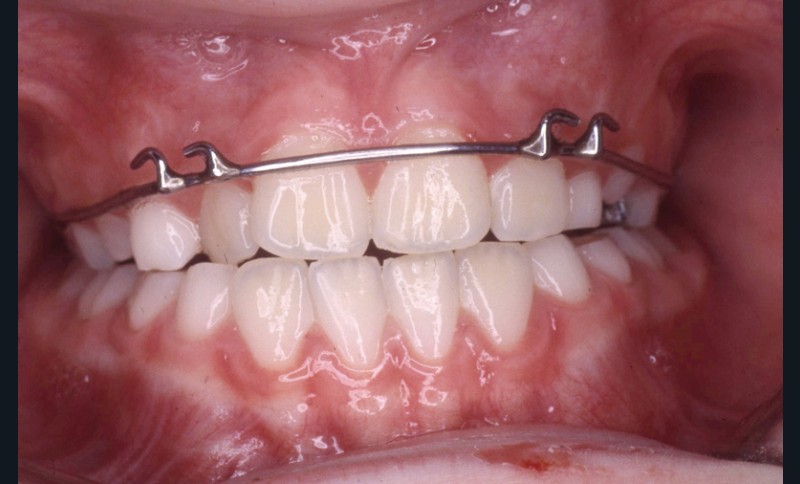

Pendant cette première étape de traitement, les tractions postéro-antérieures sont portées la nuit, soit 8 à 9 h /24 h, sur masque de Delaire pendant 13 mois, avec des tractions d’environ 800 g (fig. 7 à 9).